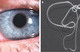

Нитеподобного паразита дирофилярию удалили в амбулатории на Соцгороде. Об этом рассказал Л. Терещенко, врач-паразитолог ВСП "Днепродзержинский городской отдел лабораторных исследований".

Гельминт передвигался под кожей 30-летнего мужчины в фиброзной капсуле. Мужчина заразился где-то в Днепродзержинске, что вызвало беспокойство санитарных врачей. Это первый случай заражения дирофилярией в городе в этом году. В 2014 году было выявлено 4 случая. На Днепропетровщине случаи заболевания дирофиляриозом регистрируют ежемесячно. За последние 12 лет случаи заражения стали чаще в 5 раз.

Дирофиляриозом, как правило, заражаются через укус комара, который перед этим попил крови зараженного гельминтом животного. Паразит развивается под кожей, может поселиться в глазу и даже в мозге. Лечение - только хирургическое удаление.